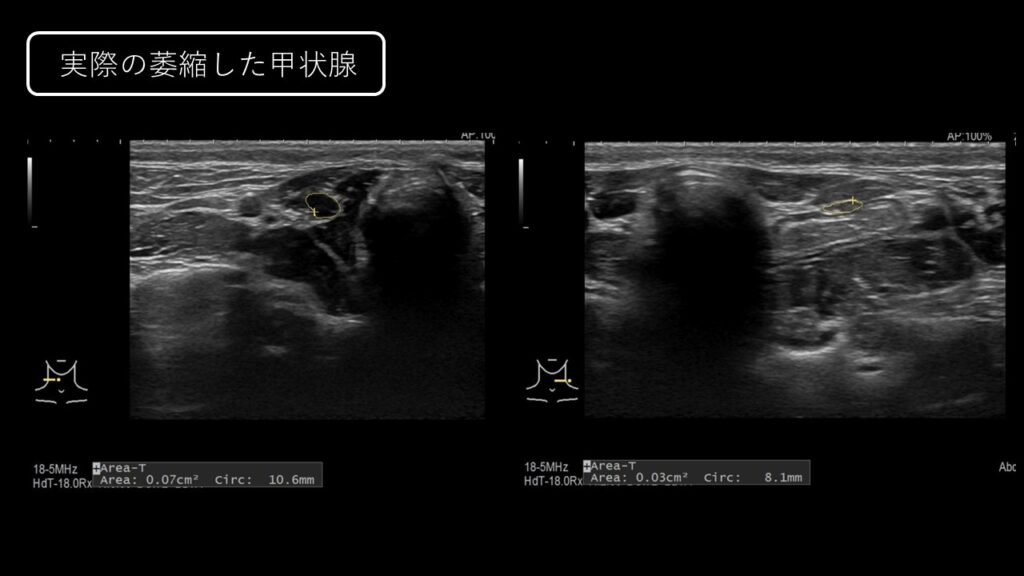

犬の甲状腺機能低下症について | 元気がないや皮膚症状は甲状腺機能低下症の初期症状かも? ~検査および診断編~

こちらの記事では甲状腺機能低下症における検査および診断について解説していきます。 甲状腺機能低下症では、様々な検査が検査が併用される場合があります。 甲状腺機…